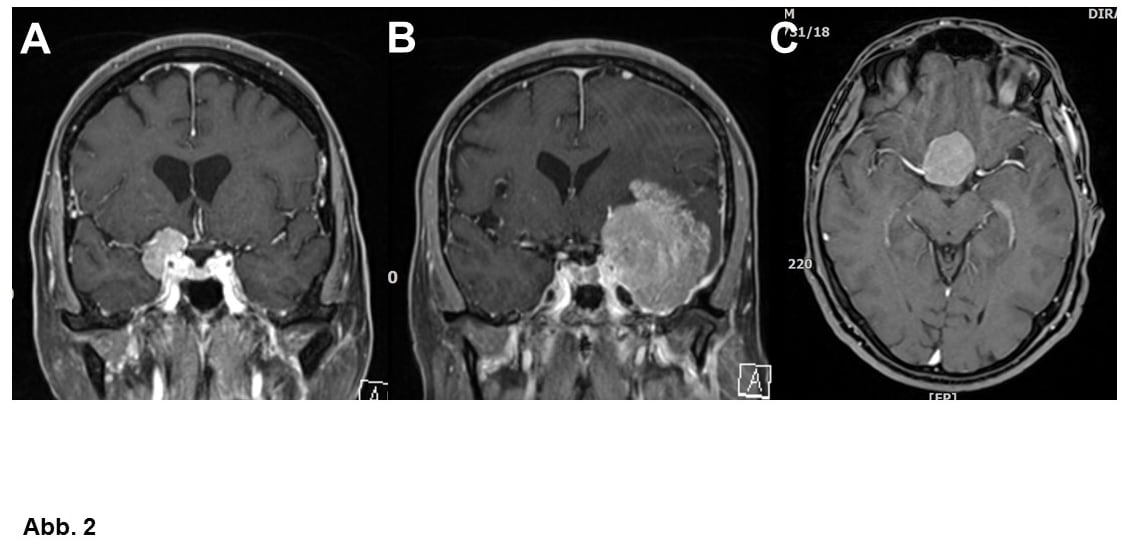

Von großer klinischer Bedeutung ist die Einteilung nach Lokalisation. Am häufigsten wachsen Meningeome ausgehend von der Hirnhaut über den Hemisphären (= Hirnhälften, Konvexitätsmeningeome, Abb. 1A-C) oder im Bereich einer bindegewebigen Sichel zwischen den Hemisphären (Falxmeningeom, Abb. 1C und D). Sogenannte Schädelbasismeningeome (Abb. 2, 3 und 4C) sind wegen ihrer Lage häufig schwieriger zu operieren als Konvexitäts- und Falxmeningeome. Meningeome können nicht nur ausgedehnt in den Hirnhäuten, sondern auch im Knochen (Abb. 4A und B) oder sogar vom Knochen ausgehend in die umgebenden Weichteile einwachsen (Abb. 4C). Meningeome im Bereich der Wirbelsäule (Abb. 5) sind seltener als im Kopf, sind aber umgekehrt häufige Tumoren im Rückenmarkskanal, wo sonst Tumoren eher selten sind. Bei bis zu 20% der Patienten liegen mehrere Meningeome vor (Abb. 1C).

Als Standardbehandlung gilt die Operation. Ziel ist die komplette Entfernung des Tumors inklusive seines Ansatzes im Bereich der Hirnhäute und eines eventuell vom Meningeom auch befallenden Knochens, wobei man natürlich das hiermit verbundene OP-Risiko gegen den Nutzen abzuwägen hat (Abb. 1-5). Deswegen ist es in manchen Fällen durchaus angebracht, ein Meningeom nicht radikal zu operieren (Abb. 6C).

A. Schädelbasismeningeom bei einer 64-jährigen Frau. Hier muß bei der Operation v.a. auf den Sehnerven und wichtige Blutgefäße geachtet werden.

B. Ähnlich gelegenes, aber sehr viel größeres Meningeom bei einer 52-jährigen Frau. Entsprechend ist die Operation bei dieser Patientin schwieriger.

C. 43-jähriger Mann mit einem weiteren Schädelbasismeningeom.